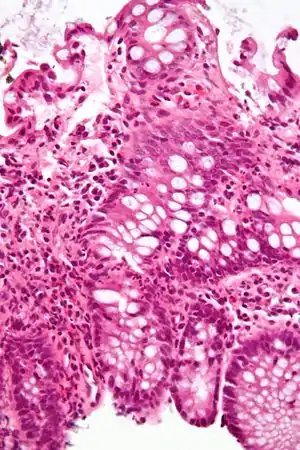

| A micrograph demonstrating cryptitis, a microscopic correlate of colitis. H&E stain. | |

An important investigation in the assessment of colitis is biopsy. A very small piece of tissue (usually about 2mm) is removed from the bowel mucosa during endoscopy and examined under the microscope by a histopathologist. It can provide important information regarding the cause of the disease and the extent of bowel damage.